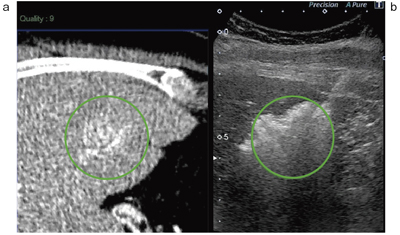

図3 CT(a)とソナゾイド造影Kupfferイメージ(b)のSmart Fusion 画面

両者の濃染像がよく一致している。

まず,ソナゾイドによる造影超音波を行うが,Aplio500では造影性能も向上しており,空間分解能も高く,肝臓の浅いところから深いところまで均一な,コントラスト分解能の良い造影像が得られている。フュージョンすると,CTの動脈相とよく一致した所見で,腫瘍の範囲がさらに明瞭になる(図3)。

治療直後に,再びSmart Fusion下のソナゾイド造影を行い,腫瘍近くの比較的太い血管が閉塞せずに残っていることが認められた。血流が増加した領域が辺縁部にリング状に見られるが,これは炎症反応を見ていると考えられる。また,この症例では十分マージンも取れていることが評価できた(図6)。

![]() 図6 RFA治療直後のソナゾイド造影超音波画像(b) 治療前の焼灼予定範囲(aおよびbの緑の円)と 治療後の実際の治療域の関係がよくわかる(b)。 |